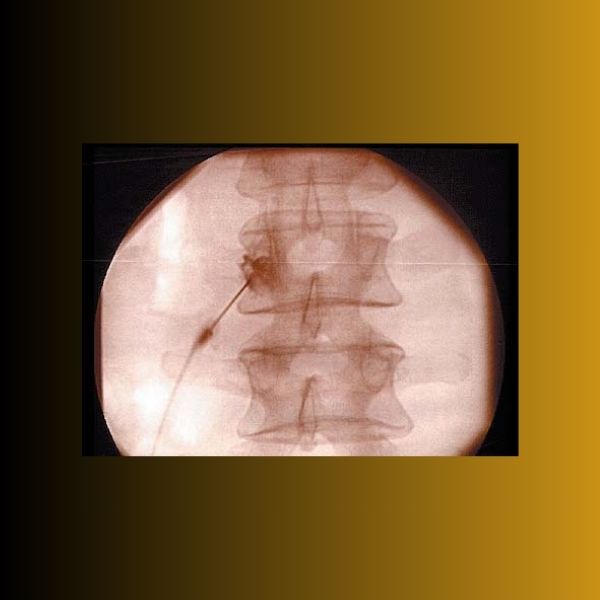

Ο ασθενής τοποθετείται σε πρηνή θέση και βρίσκεται σε ενσυνείδητη ελαφρά καταστολή. Μετά από λοξή ακτινοσκοπική λήψη περίπου 20 μοιρών, σημαδεύεται με ακτινοσκιερή μεταλλική λαβίδα στο δέρμα, το σημείο εισόδου της βελόνας, που αντιστοιχεί στο πλάγιο όριο του σώματος του σπονδύλου κάτω από την εγκάρσια απόφυση. Μετά από τοπική αναισθησία στο σημείο εισόδου και βαθύτερα στην πορεία της προώθησης της βελόνας, εισάγεται βελόνα ραχιαίας με κυρτό άκρο, η οποία προωθείται αργά υπο ακτινοσκόπηση μέχρι να έρθει σε επαφή με το σώμα του σπονδύλου. Στο σημείο αυτό η ακτινοσκοπική λήψη μεταβάλλεται σε πλάγια θέση. Το άκρο της βελόνας προωθείται ελαφρώς πιο μπροστά από το πίσω όριο του σπονδυλικού σώματος σε επαφή με αυτό. Χορηγείται 0,5 ml σκιαγραφικής ουσία και λαμβάνεται προσθιοπίσθια και ξανά πλάγια λήψη για την επιβεβαίωση της σωστής θέσης της βελόνας και στη συνέχεια χορηγείται 1ml τοπικό αναισθητικού μακράς διάρκειας δράσης για τον εκλεκτικό αποκλεισμό του αναστομωτικού κλάδου. Για κάθε επώδυνο δίσκο ο αποκλεισμός γίνεται στο επάνω και κάτω από το δίσκο σπόνδυλο, αμφοτερόπλευρα.

Η τεχνική είναι ίδια με το διαγνωστικό αποκλεισμό, με τη διαφορά ότι για την εφαρμογή της ραδιοσυχνότητας χρησιμοποιείται ειδική βελόνα με ενεργό μεταλλικό άκρο 2 mm, μέσω της οποίας εισάγεται ηλεκτρόδιο το οποίο συνδέεται με γεννήτρια ραδιοσυχνοτήτων. Αφού επιβεβαιωθεί η σωστή θέση της βελόνας γίνεται αισθητικό τεστ κατά το οποίο ο ασθενής πρέπει να αισθανθεί με χαμηλή ένταση παραισθησία, ή πίεση, ή τσίμπημα, ή πόνο στην μέση. Η θέση του άκρου της βελόνας διορθώνεται με μικρές κινήσεις μέχρι να επιτευχθεί το επιθυμητό αποτέλεσμα του αισθητικού τεστ. Στη συνέχεια εφαρμόζεται κινητικό τεστ για να ελεγχθεί αν το άκρο της βελόνας είναι κοντά σε κινητικό νεύρο πράγμα που θα προκαλέσει σύσπαση των μυών του κάτω άκρου. Αν αυτό συμβεί τότε η βελόνα πρέπει να μετακινηθεί σε σημείο τέτοιο ώστε να επιτυγχάνεται θετικό αισθητικό τεστ (παραισθησία κλπ) με χαμηλή ένταση ρεύματος και αρνητικό κινητικό τεστ με υψηλή ένταση ρεύματος( καμία κίνηση του κάτω άκρου). (1,2,8)